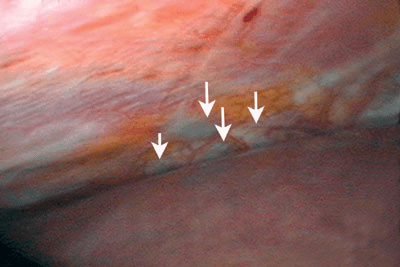

Figure 1. Les lésions symptomatiques d’endométriose du diaphragme (voir flèches) sont habituellement situées sur la partie postérieure de l’hémidiaphragme droit. Cette zone n’est pas facile à explorer à l’aide du laparoscope introduit par le nombril, mais est toujours visible lorsqu’on utilise un laparoscope de 5 mm avancé à travers la gaine musculaire située au-dessous du rebord costal droit, comme on peut le voir ici.